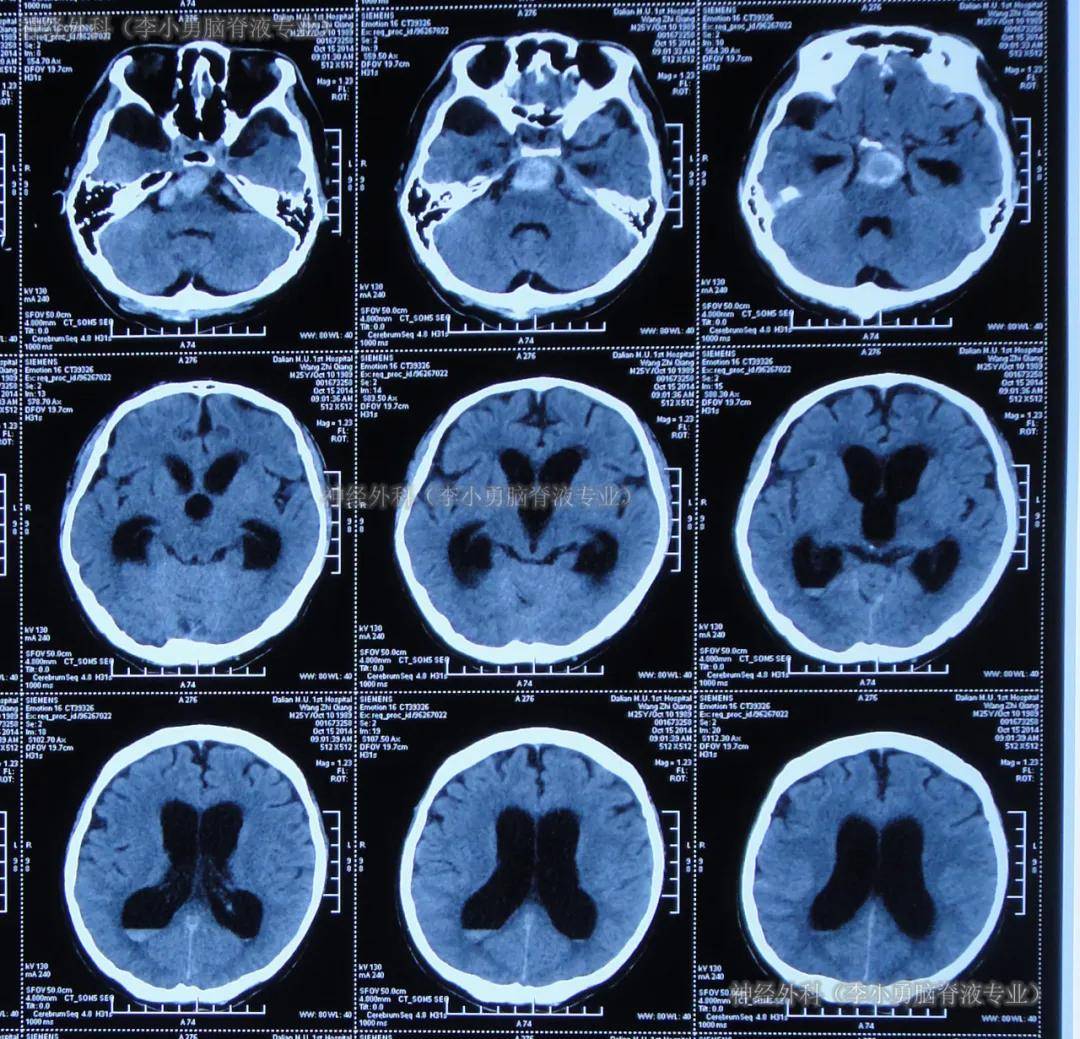

自发蛛网膜下腔出血ct影像,多为脑动脉瘤破裂出血血一一一一一神经